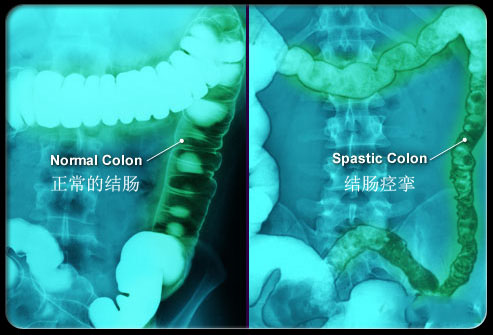

簡(jiǎn)單來(lái)說(shuō)腸道激動(dòng)就是腸道蠕動(dòng)過(guò)快或者發(fā)生痙攣,對(duì)應(yīng)最常見(jiàn)兩大癥狀腹痛和腹瀉:如下所示,腸道蠕動(dòng)過(guò)快導(dǎo)致腹瀉、痙攣導(dǎo)致疼痛。